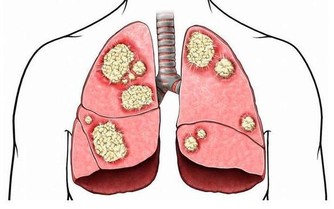

1、導致五臟中毒:長期便秘,毒素在身體內不斷地積聚,是體內五臟中毒現象,降低五臟功能,最終可能有小化大,造成其他疾病。

2、損害肝臟:便秘損害我們的肝臟功能,大便長期積於腸道,有毒物質被重新吸收入肝臟,就會損害到肝臟功能。